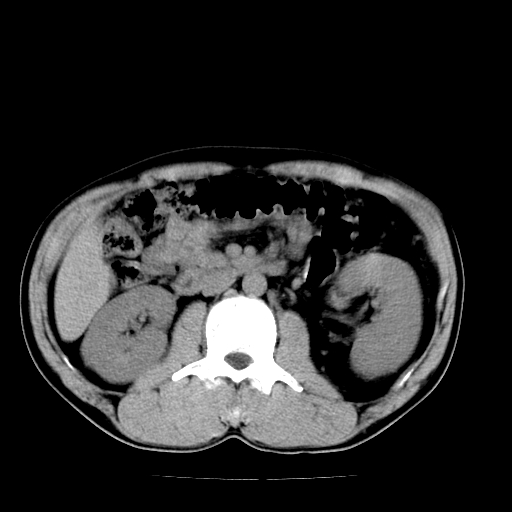

以下是引用天南地北在2007-4-30 13:36:00的发言:[br]支持慢性胰腺炎伴有假性囊肿

以下是引用andymaomao在2007-4-30 14:28:00的发言:[br]支持:1.慢性胰腺炎并假性囊肿形成可能;[br] 2.左肾形态稍增大,旋转不良。